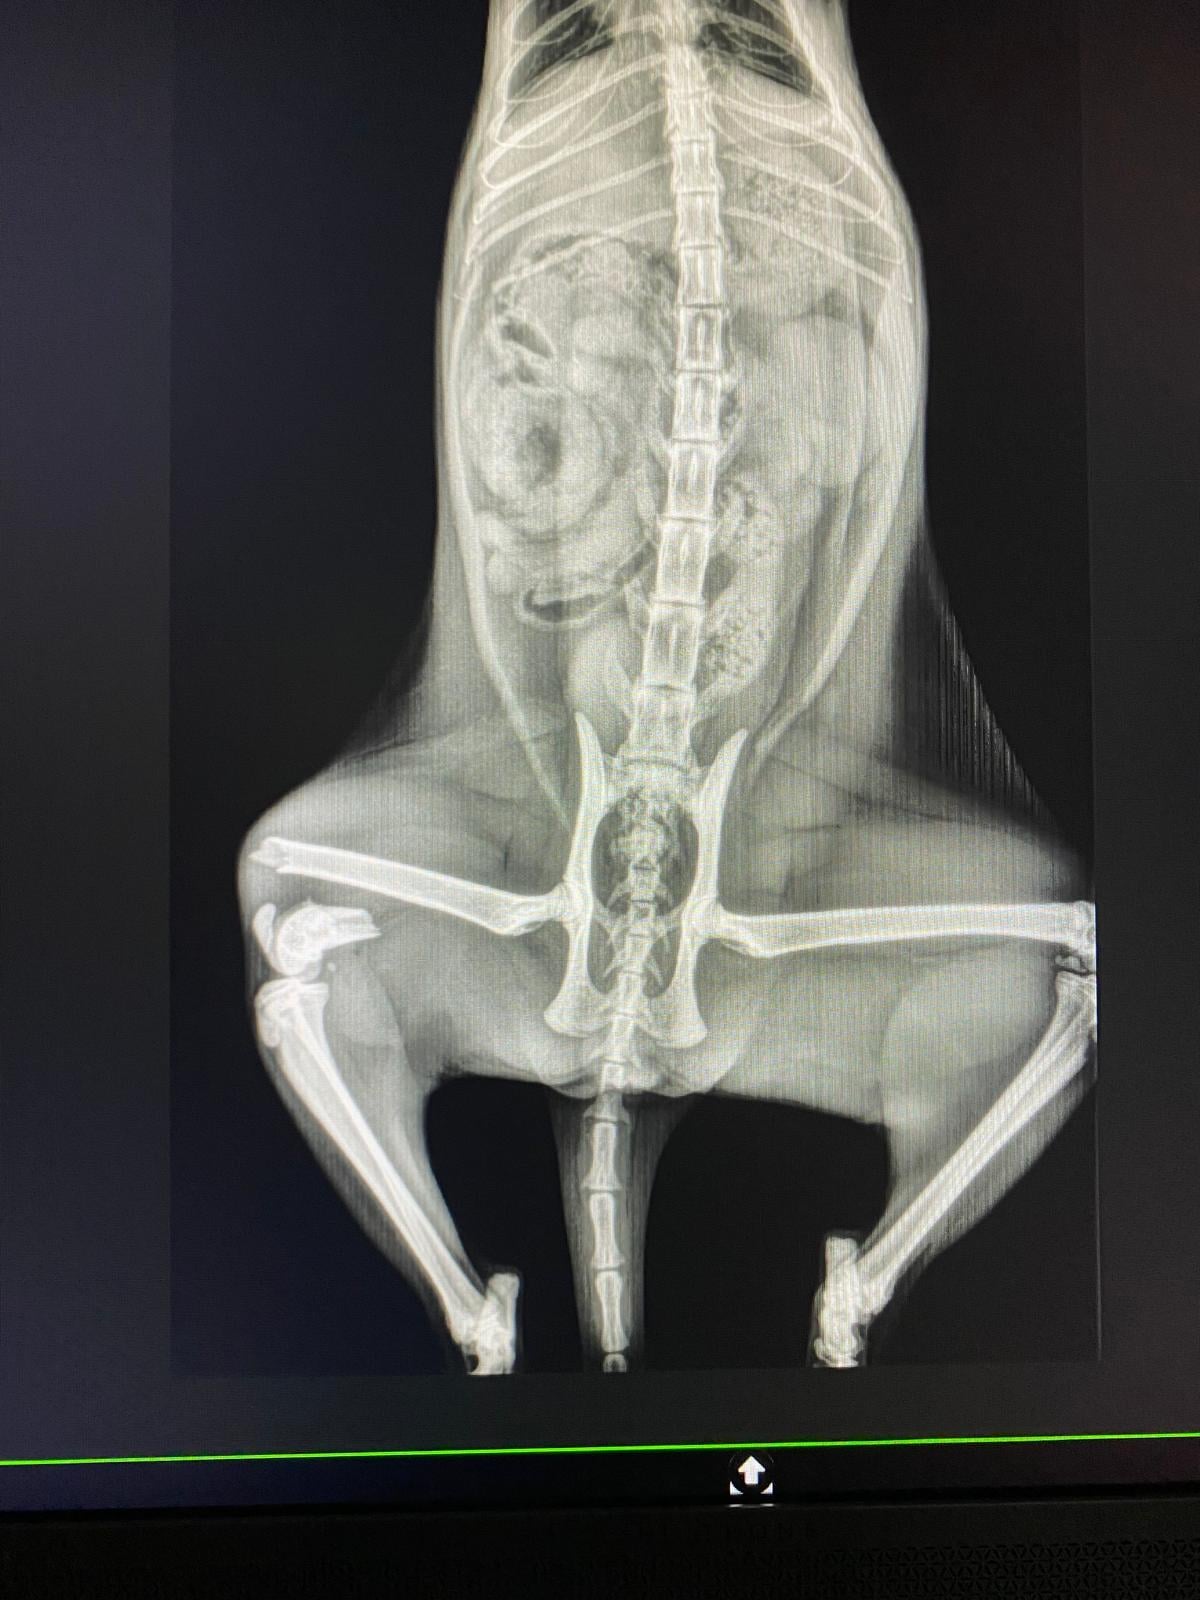

Dulcinea es una gatita de solo 6 meses , la han abandonado con una fractura tremenda, necesita una operación urgente, nos han dado presupuesto (882,84€) y no sabemos cómo hacer frente a este gasto tremendo.